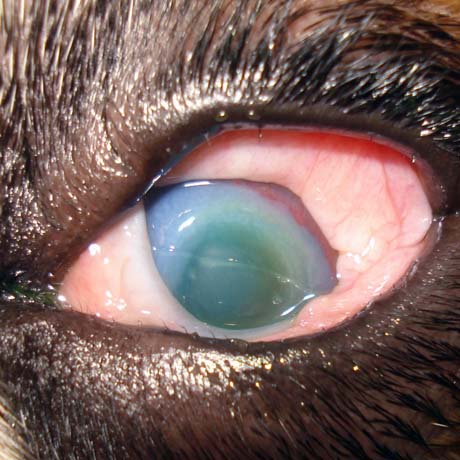

Nas patologias oftálmicas, o intervalo de tempo decorrido entre o inicio dos sintomas e a implementação do tratamento médico ou cirurgico, é fundamental para um desfecho de sucesso.